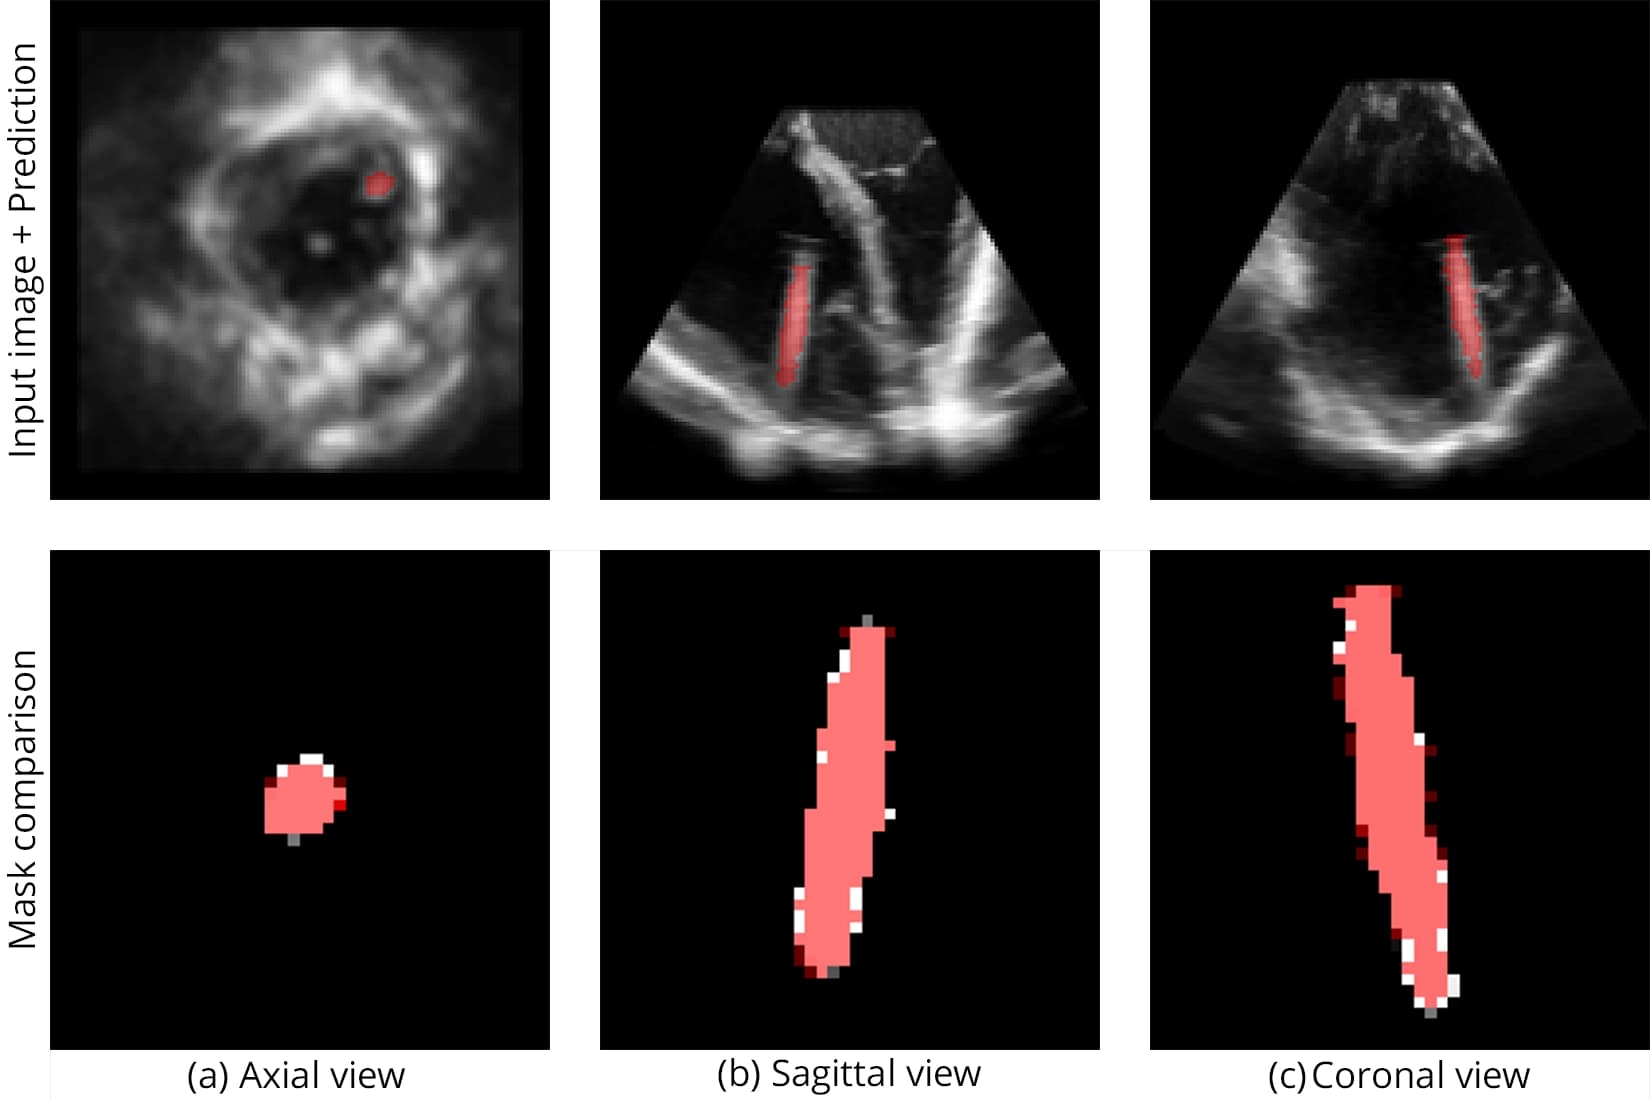

Segmentation accuracy on synthetic and real samples is shown in Figure 5 and Figure 6, and the comparison with other networks is presented in Figure 7.